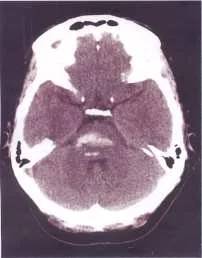

【108-2 醫學(三) 第74題】44歲女性有酗酒習慣,某日熬夜喝酒之後突然口語不清,吞嚥困難,因此被送到急診求治;患者未注射對比劑的電腦斷層掃描檢查如圖,最可能的診斷為何?

這題的解題核心在於辨識電腦斷層掃描(CT)影像中,後顱窩中央區域出現的「高密度病灶」,結合病患的急性神經學症狀,指向腦幹出血。

-A:小腦梗塞。梗塞(缺血性中風)在非對比劑CT上通常會呈現低密度(較暗),與圖片中的高密度(較亮)病灶不符。